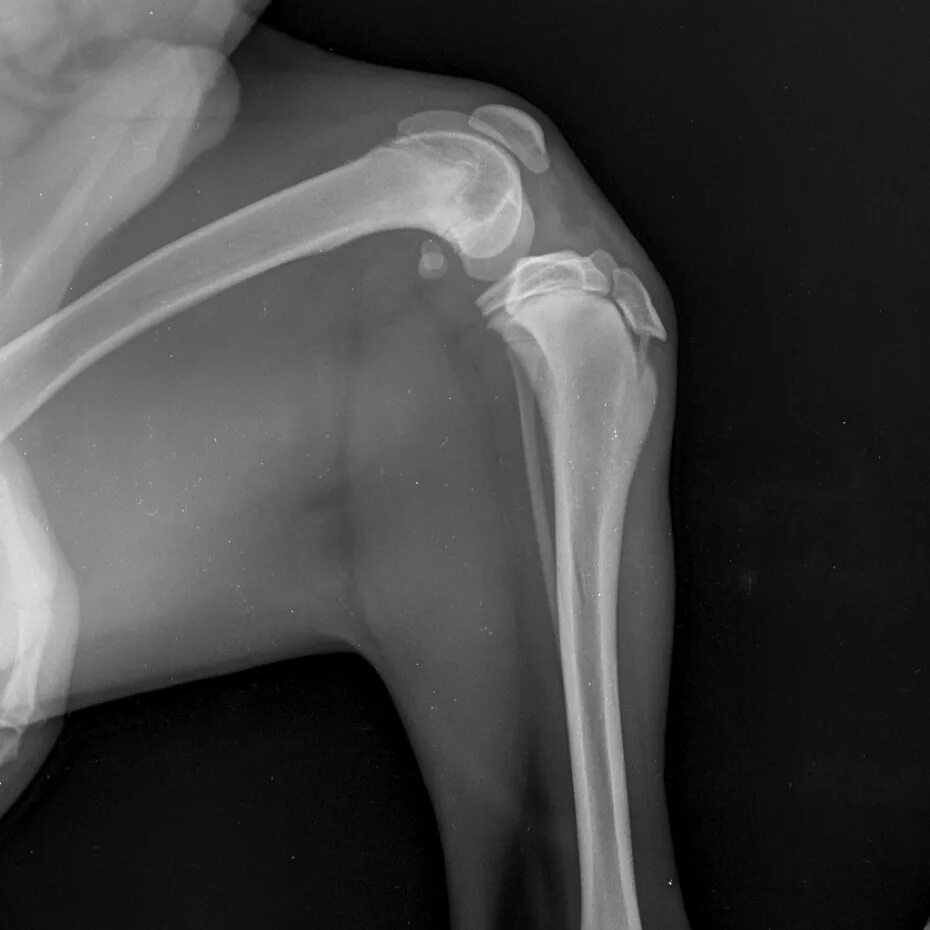

Связка кошек